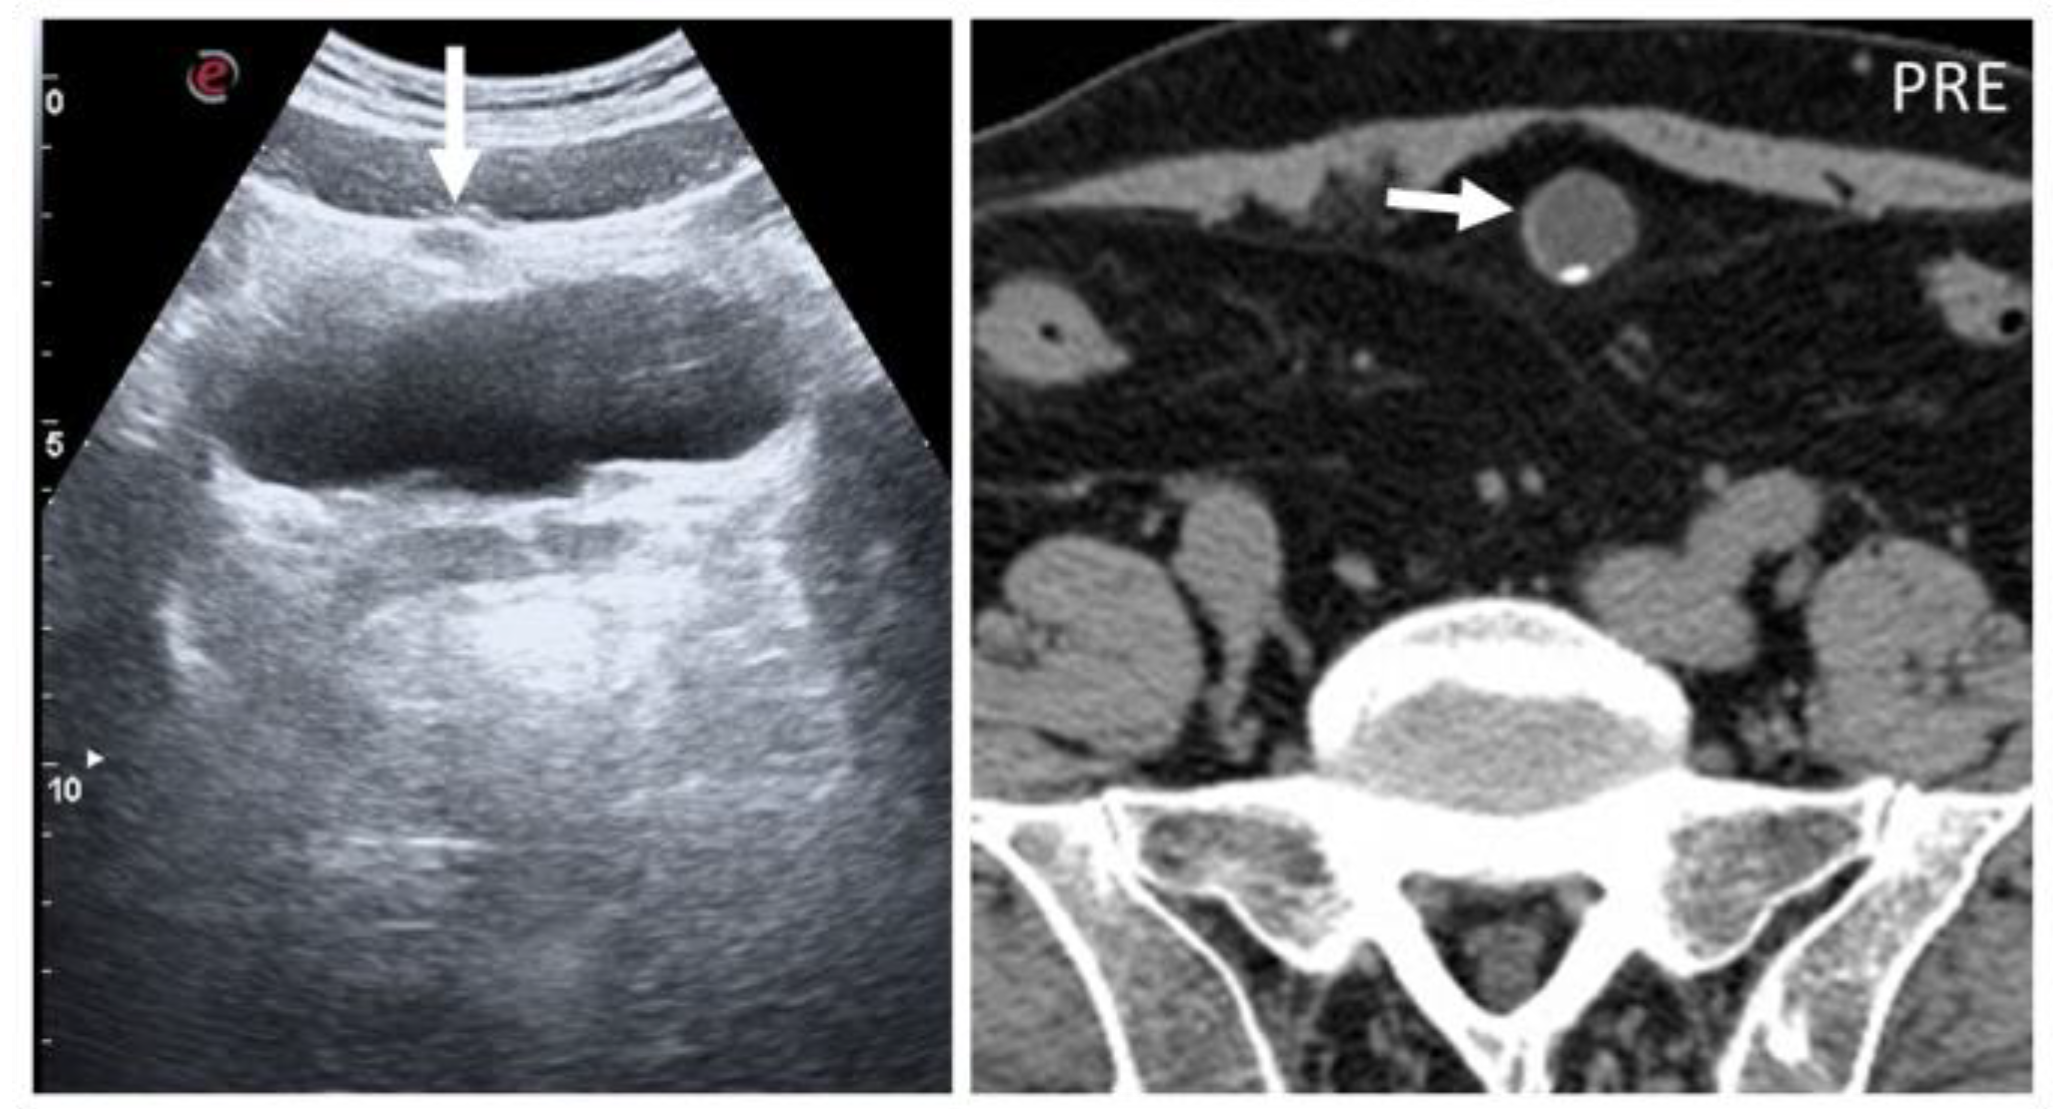

Figure 16. A 59-year-old woman who underwent splenectomy some years prior. During a CT scan, new, rounded masses (circles) were found along the peritoneum and the left rectus abdominis muscle. These formations show parenchymal attenuation on CT (pictures 1 and 2) and share the same T2 intensity as the spleen. These lesions were later characterized as splenosis.